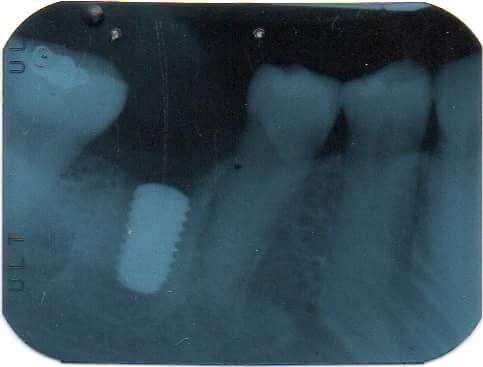

ครบ 2 เดือนวันนี้ ผลปรากฏว่า กระดูกสร้างขึ้นมาใหม่ได้ดีมาก จนเกือบเต็ม (ตามภาพที่ 2) สามารถใส่รากฟันเทียมได้เลย โดยไม่ต้องเติมผงกระดูก (ตามภาพที่ 3) ได้ประโยชน์ 2 ประการ

1. ประหยัด 10,000 บาท (ไม่ต้องจ่ายค่าผงกระดูก)

2. ไม่ต้องทนเจ็บ เพราะเมื่อไม่ต้องเติมผงกระดูก ก็ไม่ต้องกรีดเหงือก